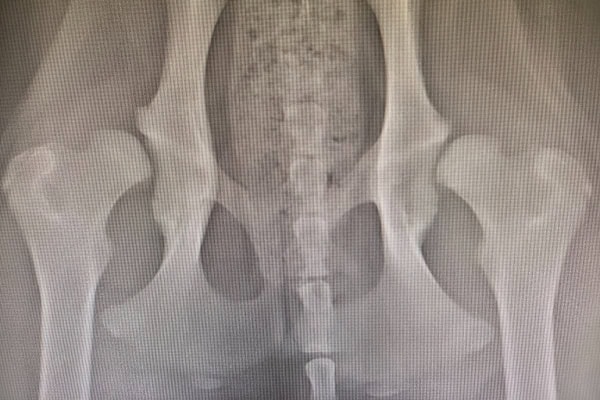

The vet will start with a physical examination, which will often provide clues to whether or not your dog has a dislocated hip. However, to reach a definitive diagnosis, the vet will likely need to take sedated X-rays. The sedation helps minimize your dog’s discomfort during the process. And it allows the veterinary team to position your dog in such a way to obtain good-quality X-rays.

The X-rays can confirm a hip dislocation and provide other valuable information. In dogs who suffered blunt trauma, they may reveal fractures of the femur and/or pelvis. This is important to know ahead of time because fractures can affect the normal shape of the hip socket and prevent a simpler, non-surgical hip reduction. X-rays are also an excellent way to evaluate your dog for hip dysplasia and other hereditary conformational issues.